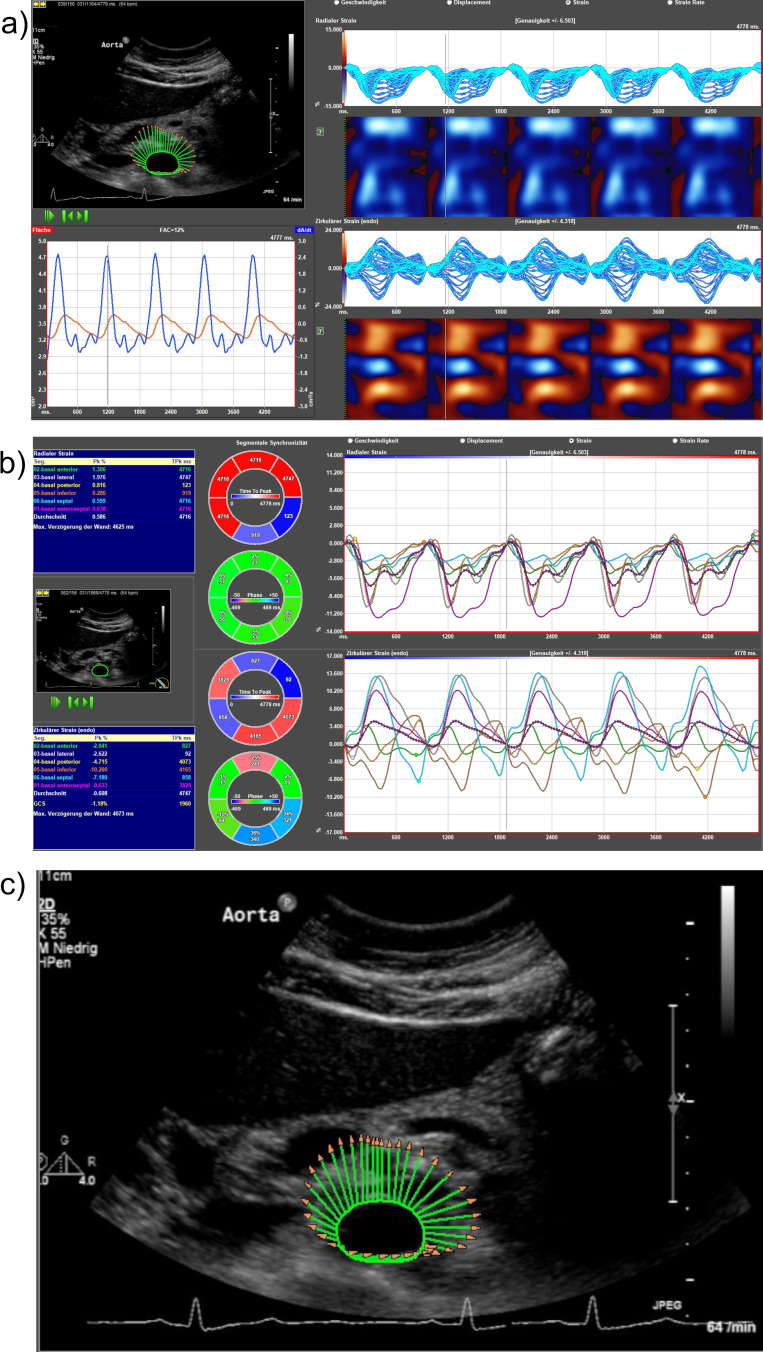

Methods: 112 outpatients were prospectively enrolled in this exploratory study. Abdominal aortic diameter was measured using ultrasonography imaging, while vascular speckle tracking was utilized to evaluate vascular strains. Patients were stratified into two groups, with n=66 patients with a BEC of ≥300 n/µL and n=46 patients with <300 n/µL. Both groups exhibited no significant disparities in cardiovascular risk factors; however, the high BEC group was more frequently male.

Results: The aortic diameter was wider in patients with a BEC ≥300 n/µL (1.46 ± 0.25 cm vs 1.67 ± 0.63 cm, p=0.018). Three patients were diagnosed with an AAA, all had a BEC ≥300 n/µL. Patients with a BEC ≥300 n/µL exhibited lower strain values, indicative of higher vascular stiffness, including radial strain (2.65 ± 1.38% vs 4.46 ± 2.59%; p<0.001). BEC exhibited a positive correlation with abdominal aortic diameter (R²=0.131, b=0.000, p<0.001), and a negative correlation with radial strain values (R²=0.131, b=-0.002, p=0.001) in sex-adjusted linear regression.